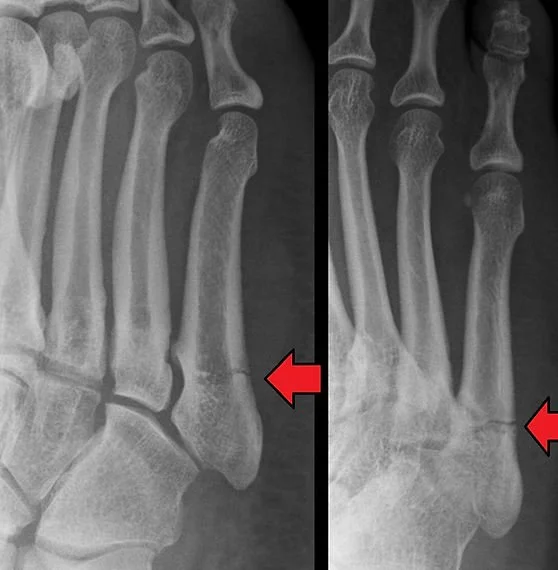

5th Metatarsal

(Jones) Fracture

A Jones fracture is a type of foot injury that affects the fifth metatarsal bone, which is located on the outer side of the foot. This fracture typically occurs from an acute injury, such as a sudden twist or impact, or from overuse and repetitive stress on the foot.